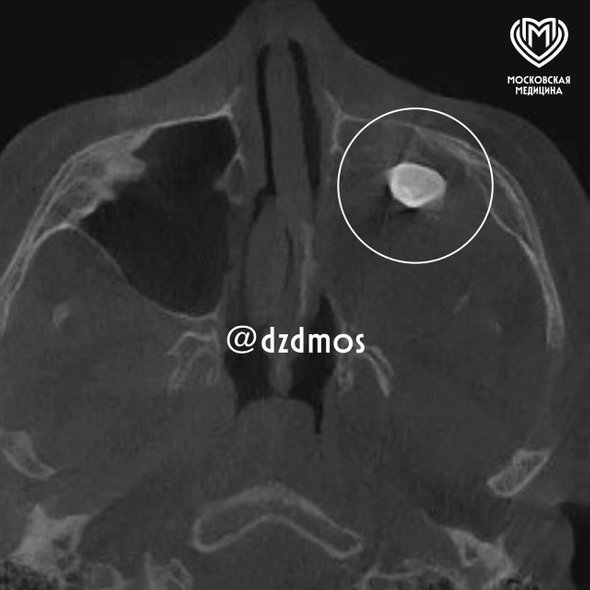

Медики собрали консилиум, заподозрив нарушение формирования зубных тканей, однако КТ и рентген не показали новообразование, заполнившее всю левую носовую полость. «Мальчику нужно было провести операцию по Колдуэлу Люку (разрез через верхнюю десну для доступа к гаймровой пазухе), чтобы вернуть ему возможность нормально дышать», — рассказали в больнице.

Внутри кистозного новообразования хирурги нашли сформированный зуб и поняли, что имеют дело с тератомой — редкой эмбриональной опухолью с элементами чужеродных тканей. Материал отправили на исследование и выяснили, что тератома доброкачественная.

«Тератомы очень редко располагаются в зоне лица, чаще в крестцовой области. Ни КТ, ни рентген новообразование не показали, поскольку оно занимало фактически всю левую полость носа. Наша осторожность полностью оправдалась, здесь было важно удалить новообразование единым комплексом, что мы и сделали. Проведение такой редкой и успешной операции стало возможным благодаря работе мультидисциплинарной команды», — добавил хирург-оториноларинголог Вугар Достиев.

фото: t.me/dzdmos